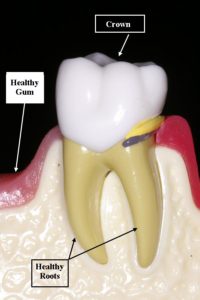

A destructive infection of the gum and underlying bone. It is gingivitis that has gotten out of control and has started to destroy the connection between the gum and the tooth. It is characterized by red, swollen and bleeding gums and will result in tooth loss if it is not treated. The infection causes the bone and ligament which hold the tooth in place to be destroyed. It is also known as periodontal disease and Pyorrhea. How aggressively the infection destroys the bone and gum which support the teeth is influenced by whether or not the patient smokes, if they are diabetic, if they are genetically predisposed, if they are on certain medications and if they clench and grind their teeth. Gum infection has also been linked to cardiovascular disease, stroke, low birth weight and preterm newborns, difficulty in controlling diabetes and recent evidence suggests it may affect Alzheimer’s and upper respiratory tract infections.